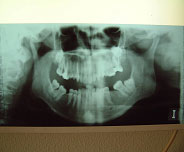

La angulación de los cóndilos en el plano axial (12), el insuficiente desarrollo de los cóndilos (Hipoplasia) (13, 14), son factores que favorecen la aparición de patología y más aun si se añaden sobrecargas funcionales. Un cóndilo hipoplásico (Fig. 1) nos obligará a proteger más las articulaciones durante la realización de las higienes dentales, para no sobrecargarlas y favorecer así la aparición de patología.

Fig. 1 Hipoplasia Condilar